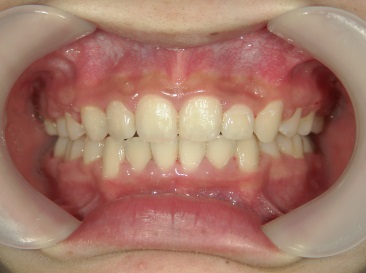

矯正歯科 治療後矯正歯科 全顎ワイヤー矯正 治療後矯正歯科(全顎ワイヤー矯正)治療後

矯正歯科 治療後

no.18_2196_治療後_右.jpgno.18_2196_治療後_正面.jpgno.18_2196_治療後_左.jpg